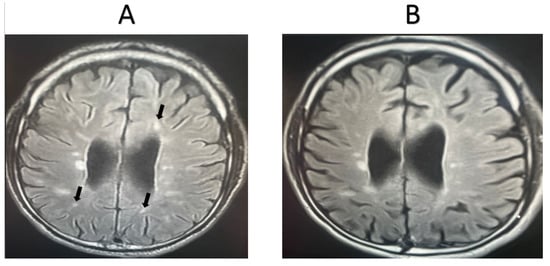

3.2. Magnetic Resonance Imaging Results